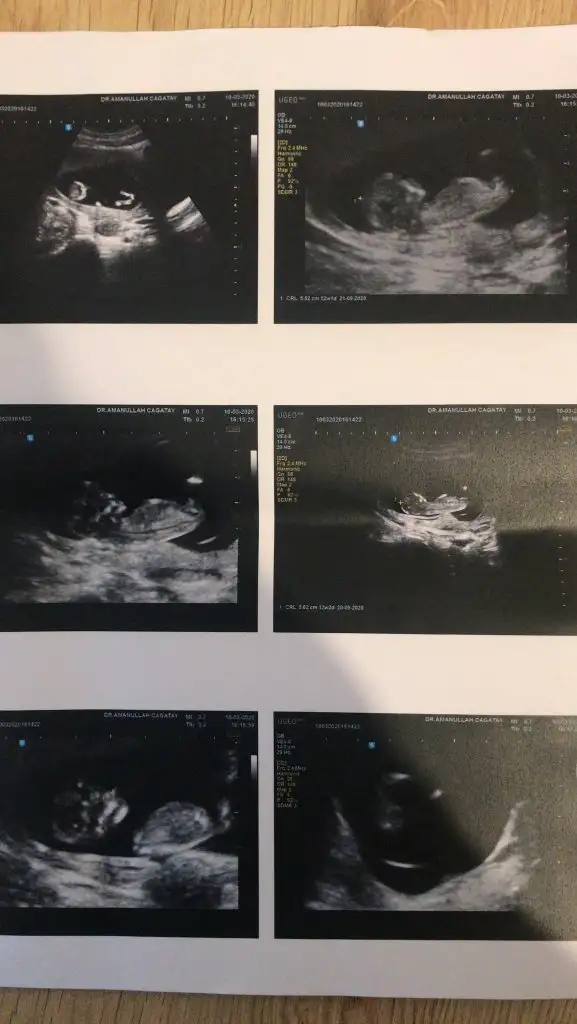

Kız sanki emin olamadım başka usgde paylaşınKızlar tahminde bulunabilirmisiniz ikiz bebekler 12 hafta 1 gunlikler

rBu kadar usg görüntüleri var malesef

Çift yumurta ikizleriTamam tüp olabilirde tek yumurta yada çift yumurta bebegimi onu sordumsaglıkla gelsin minnoşlar

9+3 haftada nub tahmini olmuyor nub için 11 yada 12 yada 13 haftaları paylaşınelimdeki tüm usg görüntüleri bunlaryeterli olur mu ki tahmin için